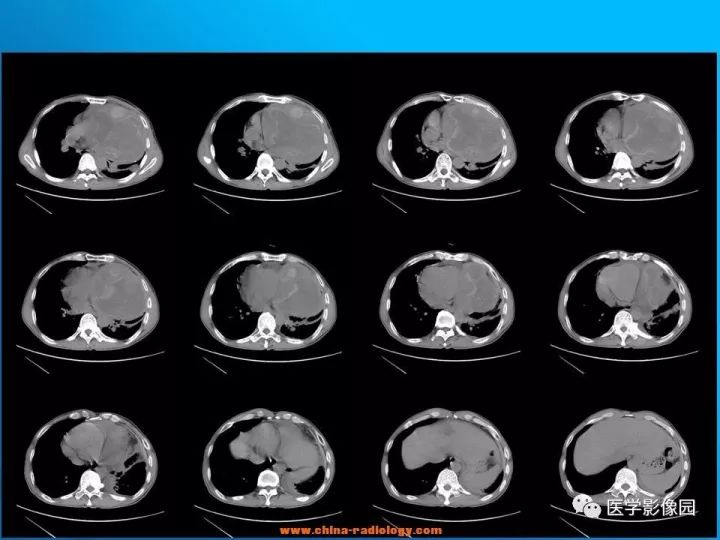

【病例】纵隔恶性神经鞘瘤1例CT

诊断结果:恶性神经鞘瘤

CT表现

2.增强扫描多数病例肿瘤强化轻微,包膜可强化,少数病例可有较明显强化。

3.当肿块体积较大,并向周围侵犯,其内密度混杂,尤其是囊变、坏死明显;实性部分呈斑片状及网格状较明显强化;往往提示为恶性神经鞘瘤。